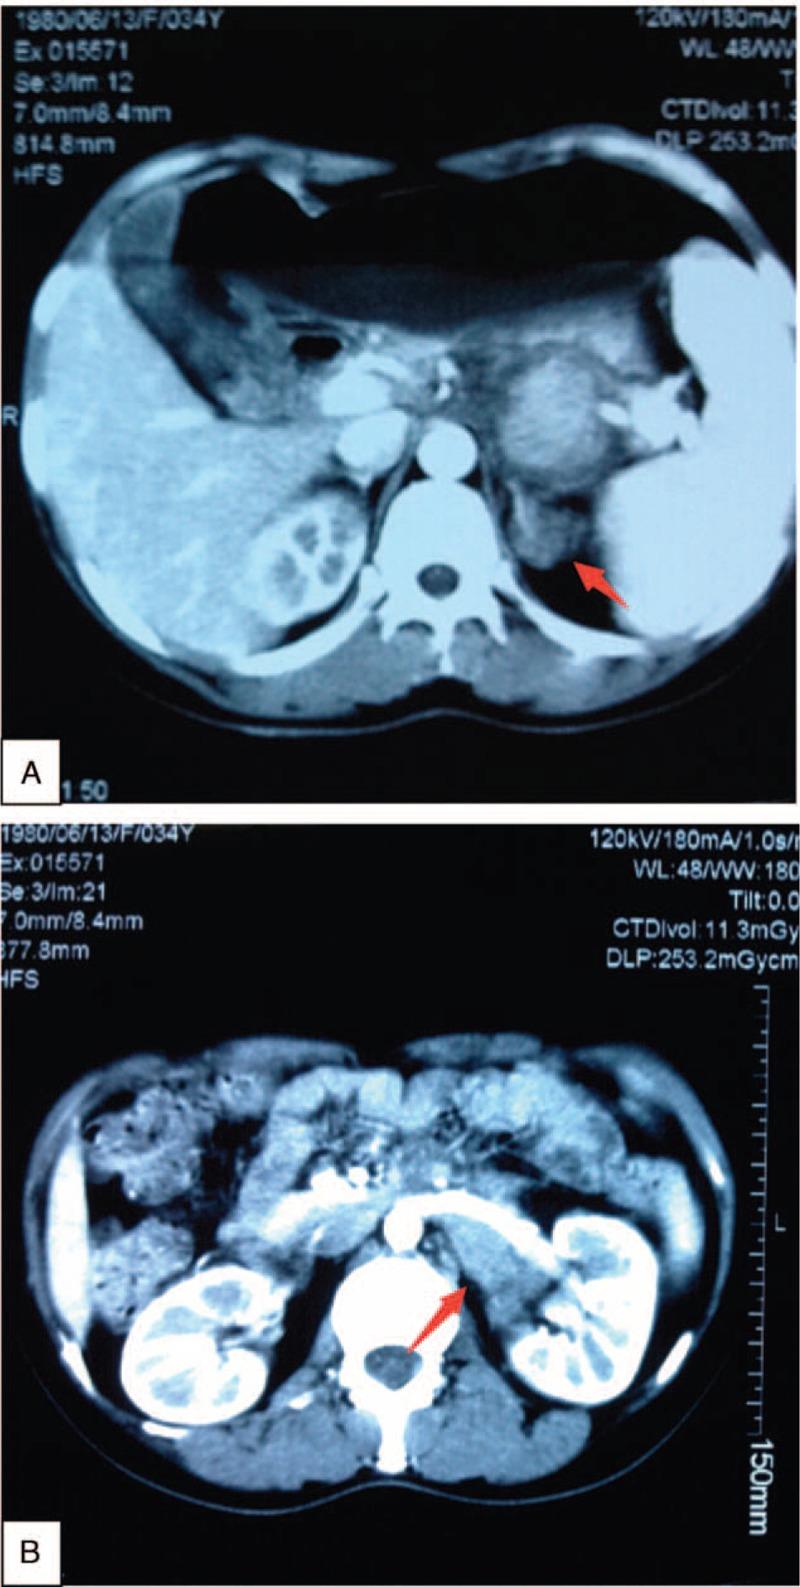

Inflammatory myofibroblastic tumor (IMT) rarely arises in genitourinary tract especially beyond collecting system, which determines the unspecific clinic symptoms and sometimes can mimic malignancy. Therefore, IMT's diagnosis may usually be a pitfall. This case report characterizes a 35-year-old woman with a history of lower quadrant lasting pain followed by fever. Furthermore, radiologic examinations revealed that there were 2 lesions located in left adrenal area and left renalis. Owing to the anatomic complexity, the surgical resection was not complete. The pathologic diagnosis of the lesions was IMT. Adjuvant nonsteroids anti-inflammatory drugs were administrated after the operation. The symptoms were controlled finally and no further growing lesion was observed during a 1-year follow-up.Inflammatory myofibroblastic tumor is rare in genitourinary tract beyond the collecting system. Diagnosis should be based on histopathology. Presently, the authors report this rare case with the aim to share the experience regarding differential diagnosis and therapy.

炎性肌纤维母细胞瘤(IMT)很少发生于泌尿生殖道,尤其是集合系统以外的部位,这导致其临床症状不具特异性,有时可能类似恶性肿瘤。因此,IMT的诊断通常可能存在陷阱。本病例报告描述了一名35岁女性,有下腹部持续疼痛伴发热病史。此外,影像学检查显示左肾上腺区和左肾有2个病灶。由于解剖结构复杂,手术切除不完全。病灶的病理诊断为IMT。术后给予辅助性非甾体抗炎药。症状最终得到控制,在1年的随访中未观察到病灶进一步生长。炎性肌纤维母细胞瘤在集合系统以外的泌尿生殖道中罕见。诊断应基于组织病理学。目前,作者报告此罕见病例旨在分享鉴别诊断和治疗方面的经验。